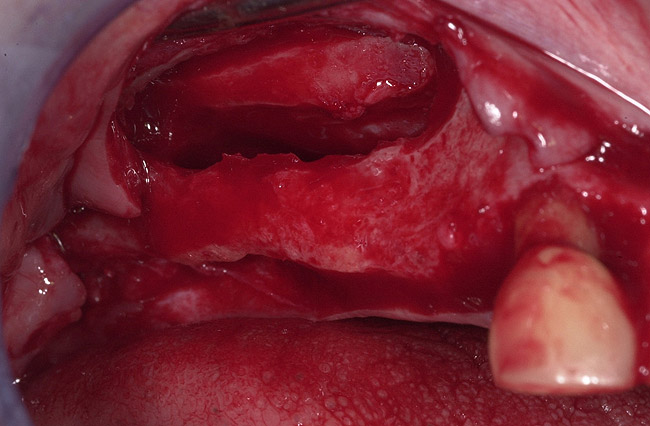

Figure 22  Sinus septum evident at site No. 3.

Figure 22

Figure 23  First, the sinus septum was identified.

Figure 23

Figure 24  Then, the septum was isolated.

Figure 24

Figure 25  Lastly, the septum was managed.

Figure 25

Figure 26  Bong graft was placed in the mesial and distal compartments.

Figure 26